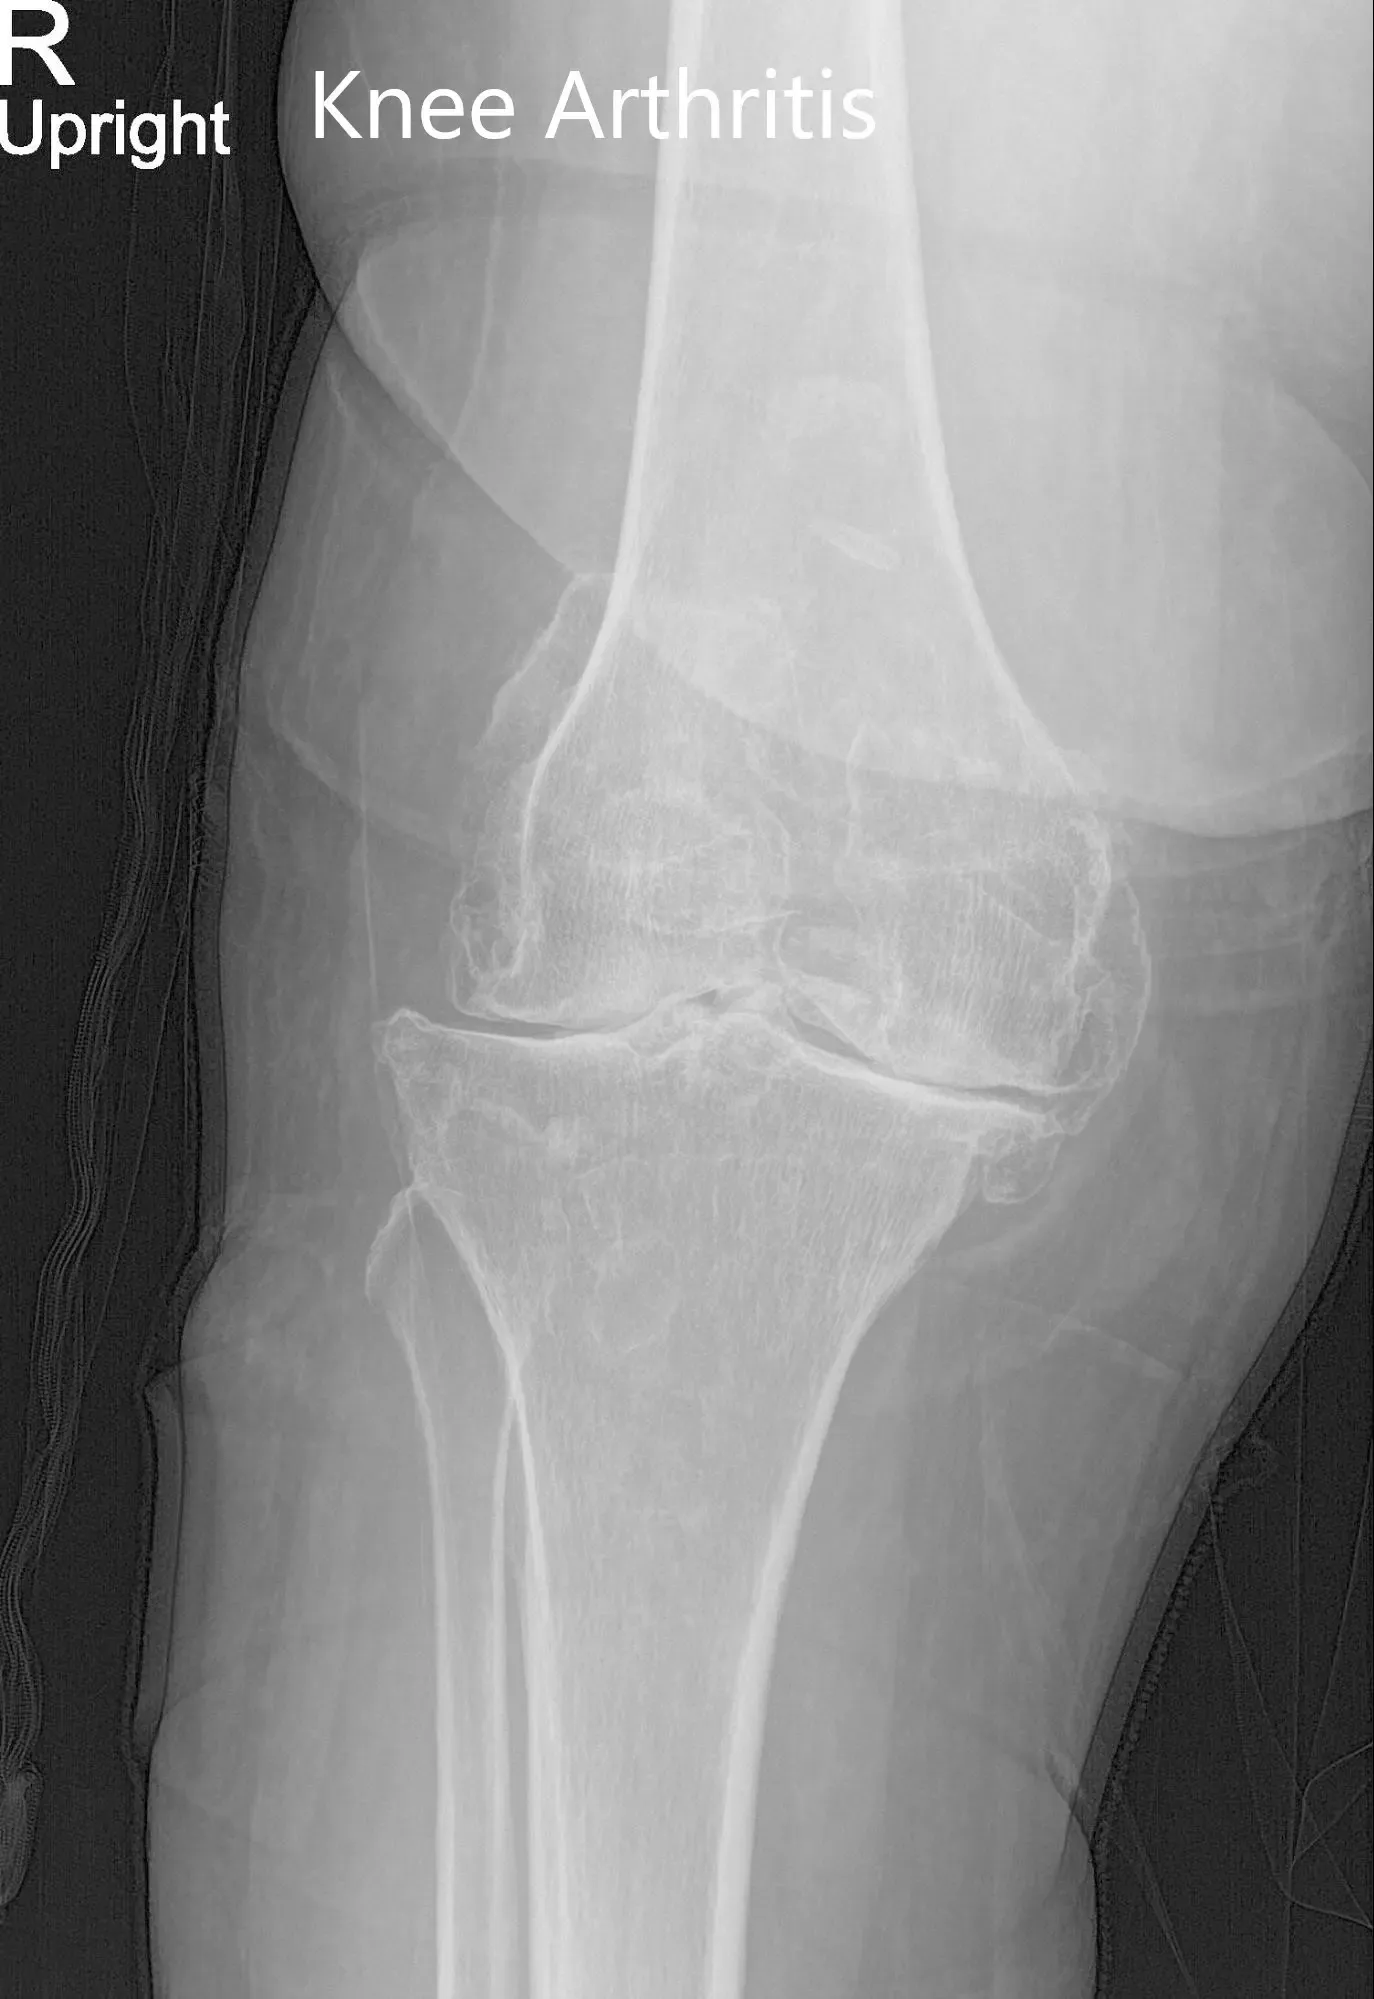

Preoperative X-ray of the right knee showing AP and lateral views

His physical examination revealed severe arthritis of the bilateral knees. There was mild swelling bilaterally with no rise in temperature or erythema. The overlying skin of bilateral knees was normal. There was tenderness on the medial joint line and patellar facet (right greater than left).

Genu varus deformity was present with a restricted range of motion due to pain (right – 0 to 95 degrees and left – 0 to 100 degrees). There was no coronal, sagittal or rotational plane instability or laxity. The distal neurological examination was normal bilateral. Distal lower extremity pulses were 2+ and palpable.

His imaging studies revealed severe tricompartmental osteoarthritis of the bilateral knee joint. After careful consideration of his medical conditions and needs, he was advised bilateral custom total knee replacement. He was made aware of the increased risk associated with bilateral surgery. Alternatives, risks, and benefits were discussed in detail with him and his son. They agreed for the procedure.